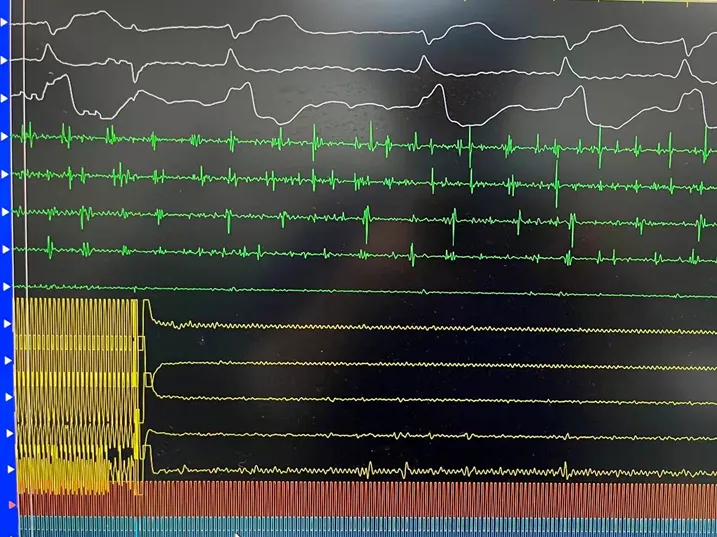

手术在全麻下进行,消融策略涵盖双侧肺静脉、左房后壁及上腔静脉,总计消融73个位点,累计消融时间仅146秒。术中活化凝血时间(ACT)维持在250-300秒,未出现并发症。消融结束后,患者仍为房颤心律,经电复律成功转为窦性心律,手术顺利完成。

六瓣花导管呈网篮及花瓣形态放电

LSPV消融及前后电位对比

LIPV消融及前后电位对比